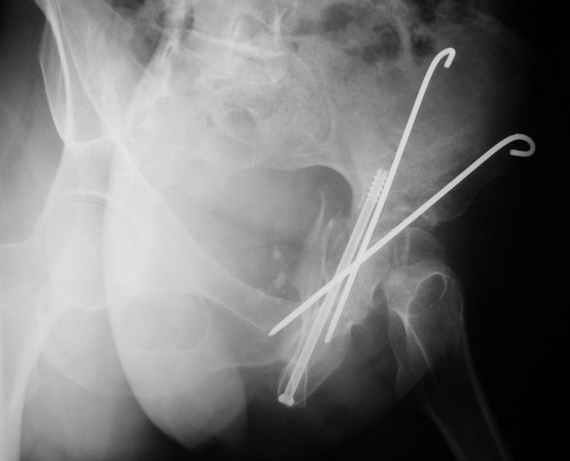

Уважаемые коллеги,Мужчина 36 лет от роду попал в ДТП 24.08.04 Рентгенограммы в приложении.

Диагноз- перелом с вовлечением таза, разрыв правого сакро-илиак сочленения vertical shear injury, перелом крыла подвздошной кости?, перелом ацетабулум Т type или Both column?, перелом шейки бедра, перелом проксимального отдела бедра.

перелом крыла правой подвздошной кости, перелом обеих колонн вертлужной впадины, двусторонний перелом лонных костей (С2.2) повреждение передних связок правого крестцово-подвздошного сочленения,

ипсилатеральный перелом шейки и диафиза бедра.